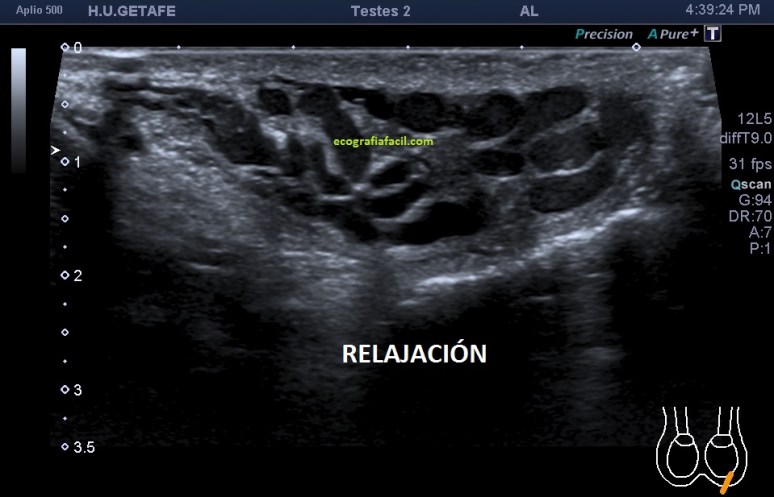

Varicocele: Estrella invitada de muchas exploraciones de escroto que llegan a la sala. Por eso lo he dejado para el final. Es la colección de venas agrandadas, tortuosas y anormalmente dilatadas.

En la imagen 15 puedes ver una imagen bastante sugerente de varicocele, en esos vasos anecoicos e hipocogénicos podemos encontrarnos un movimiento lento de la circulación sanguínea visible sin necesidad de doppler en relajación, pero que cambia su aspecto con el modo doppler y/o modo angio y con maniobra de valsalva como ves en la imagen 16. Hay diferentes grados, nosotros debemos documentar todo de manera correcta para que la radióloga pueda evaluar y definir el nivel o grado de dicho varicocele.